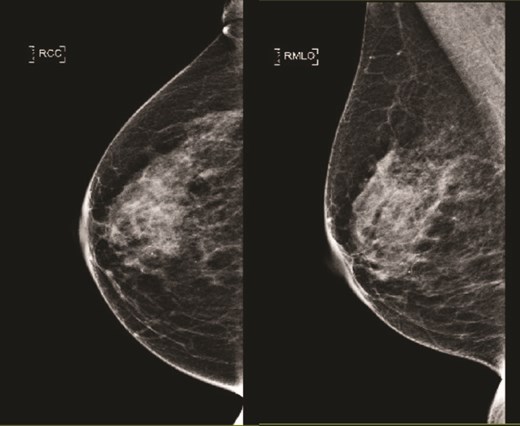

(Left) Breast core biopsy showing periductal atypical lymphoid proliferation. (H&E stain, 20 times magnification); (Right) Breast core biopsy with immunohistochemical staining showing atypical lymphoid cells positive for CD20 stains.

(Left) Breast core biopsy showing follicular hyperplastic nodules of atypical lymphoid cells (H&E stain, 40 times magnification); (Right) Breast core biopsy with immunohistochemical staining; atypical lymphoid cells forming hyperplastic nodules positive for CD20 stains.